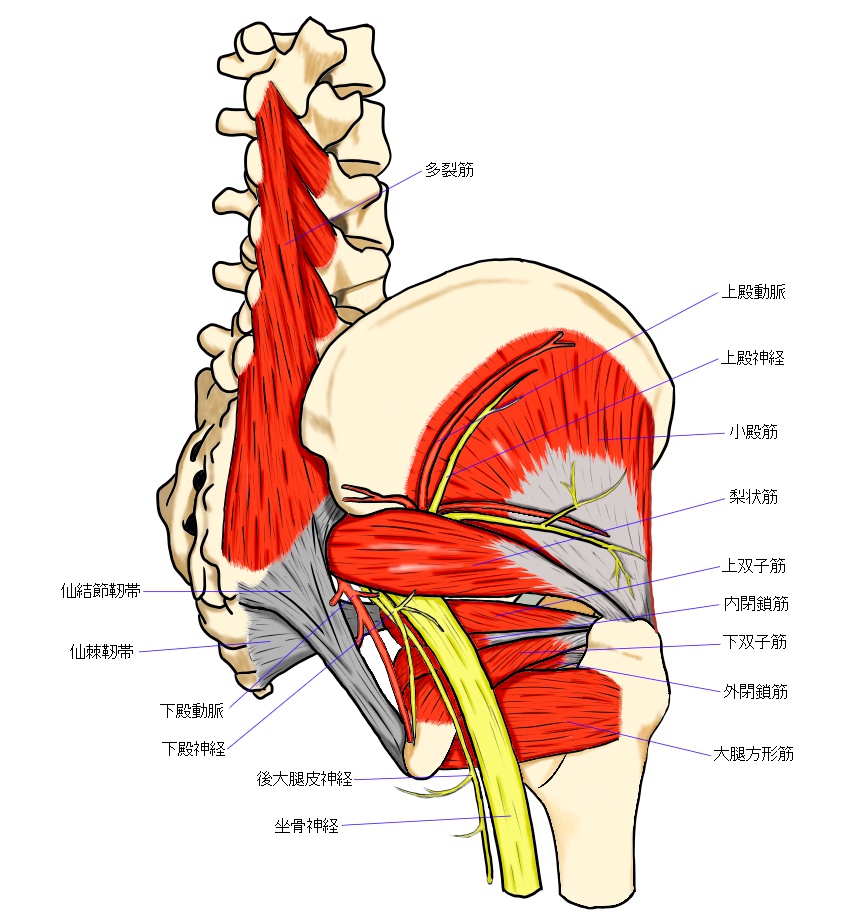

正解は坐骨神経のスタート(仙骨神経叢)は脊柱から始まり、腰や骨盤の間を抜けて走行していきます。

詳しい場所で言うと、脊髄から分岐した神経が腰椎の下部(椎間孔)と仙骨(骨盤)の裏側の仙骨孔と呼ばれる穴から出てくるのが始まりです(L4ーS3)

腰椎や仙骨(骨盤)裏側から出てきたにもかかわらず、1度骨盤の内側に入っていきます。

このまま骨盤の前側のほうに抜けていきそうですが、そこからまた行く先を変え、仙骨と腸骨の間にある大坐骨孔と言う穴を抜けて身体の後ろ側に戻ってきます。

そこから先は、みなさんの想像されるであろう場所を通っていきます。

お尻の梨状筋と言う筋肉の間を抜けて、お尻の下、太ももの裏へと流れていきます。

その後、膝の裏あたりまでまっすぐと進み、その先は「脛骨神経(けいこつ)と総腓骨神経(ひこつ)」と分岐していきます。

圧迫や原因になりやすい代表的な筋肉が2つあります。

1つは梨状筋(お尻の中央を横断する筋肉)、もう1つはハムストリング(太ももの裏側を走る大きな筋肉)です。

股関節の可動域が狭くなったり、太ももの裏側の筋肉が張って硬くなることで、その間を通る坐骨神経が直接圧迫や牽引がかかります。

・腰椎や骨盤を出てすぐの所(椎間孔、仙骨孔)

・梨状筋の周辺

・坐骨結節の上側

・ハムストリングの間